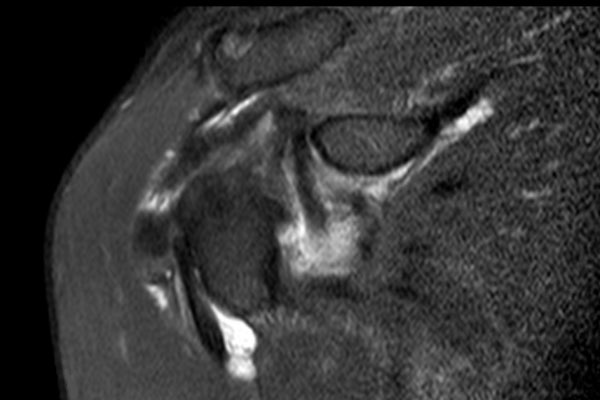

Hình ảnh

Chuỗi xung T2W xóa mỡ mặt phẳng axial và chuỗi xung PD mặt phẳng sagittal chếch.

Có hình ảnh rách không hoàn toàn gân dưới vai kết hợp với phù nề do gãy mấu động nhỏ (lesser tubercle).